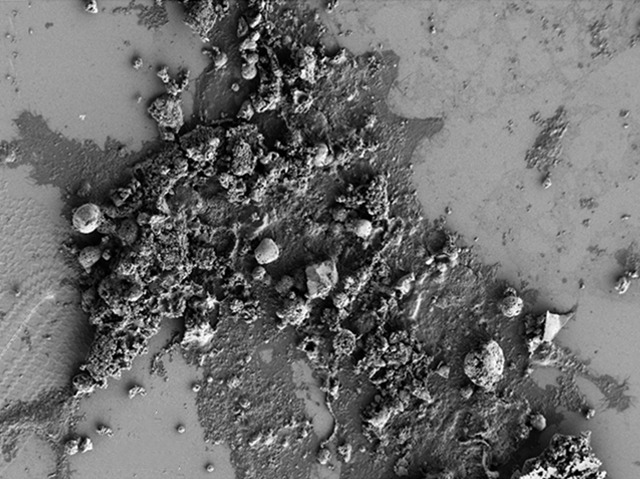

Road Block

Out on the road, closed lanes and other obstructions cause frustration and delays, often forcing traffic to grind to a halt. More worryingly, the same problems can occur within our arteries, the network of vessels that supplies our organs with oxygen and nutrients. In the process of vascular calcification (VC), crystals of calcium phosphate (pictured) aggregate inside the vessels’ walls, impeding circulation. The consequences are predictably devastating; in patients suffering from chronic kidney disease, VC is the main cause of death. Research has shown that crystal formation is not a passive process, but rather that smooth muscle cells surrounding arteries can actively influence their deposition. This means there could be ways to influence cells so that calcification is reduced; for example, the presence of magnesium is known to alleviate symptoms. Understanding how this works, and what other factors are involved, will help devise means of slowing this deadly process.